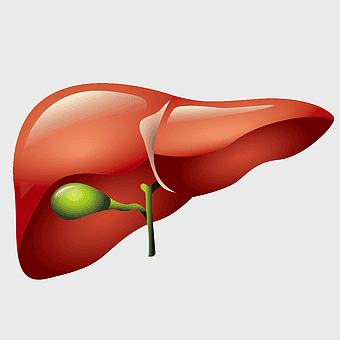

liver illustration, human liver cartoon, cartoon liver image, liver organ diagram, liver anatomy visual, medical liver graphic, liver health depiction -

liver with gallbladder diagram, human liver function, bile production organ illustration, digestive system anatomy, liver and bile duct visual, human anatomy medical graphic, hepatology reference image -